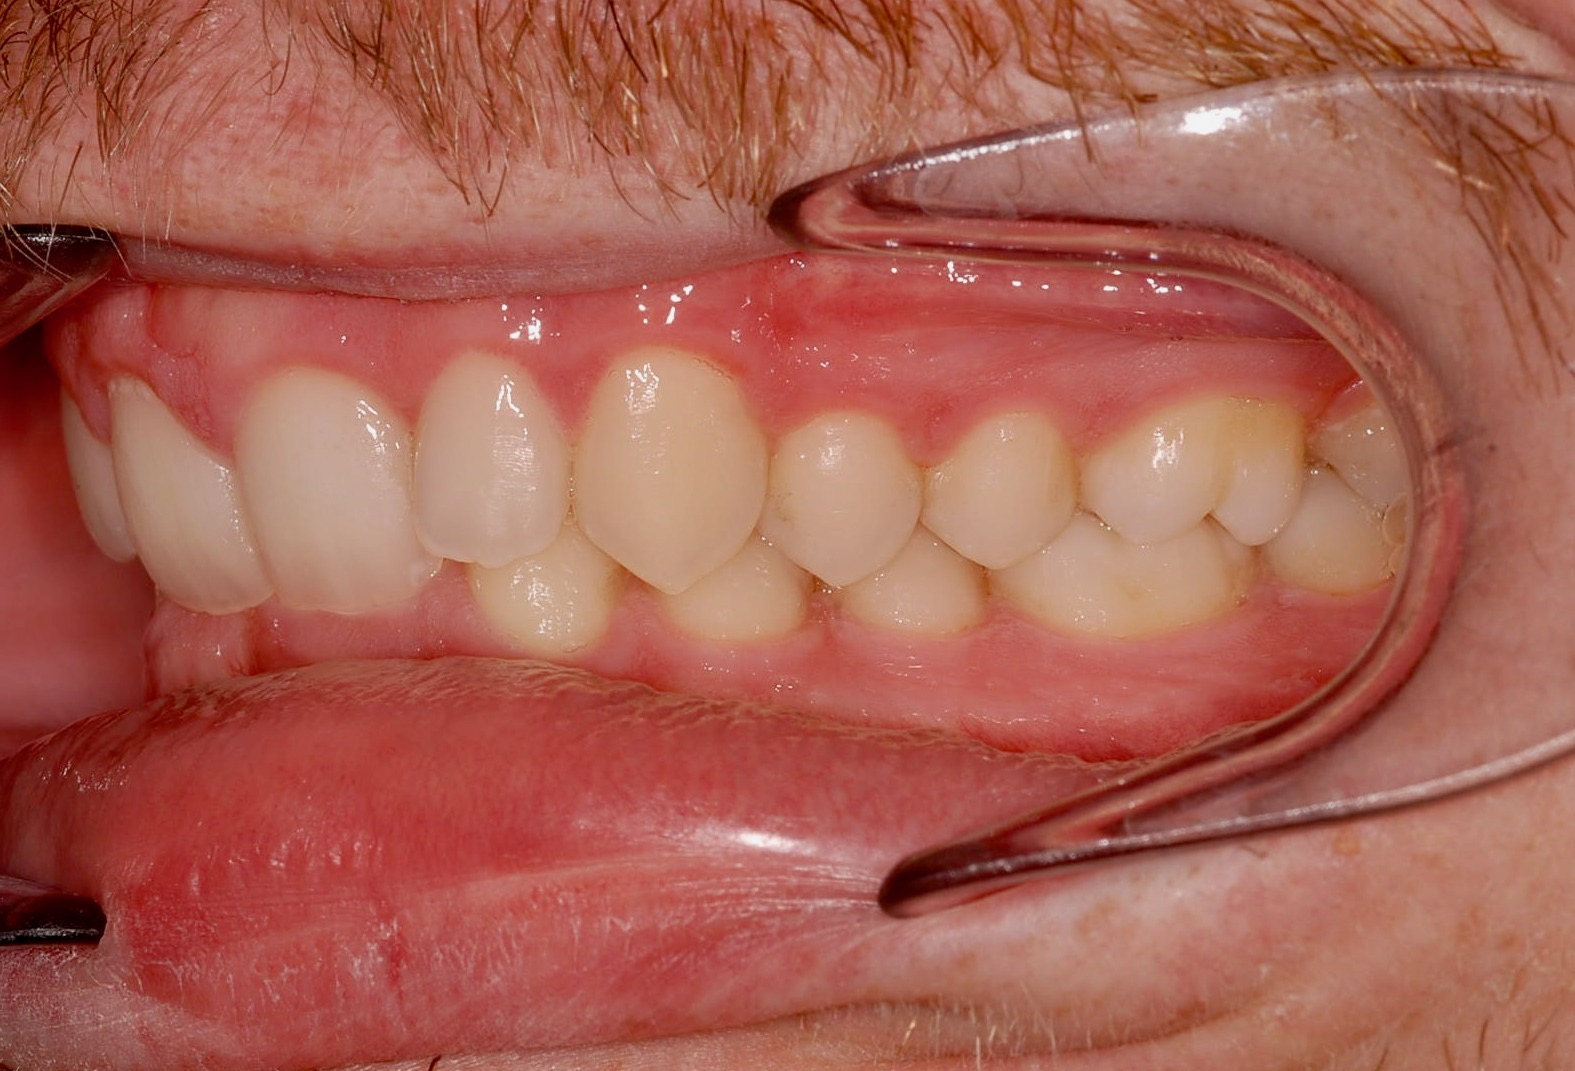

Class II subdivision malocclusions can be difficult to treat because of their asymmetric occlusal relationships. An accurate diagnosis, etiologically based when possible, is essential to perform a correct and efficient orthodontic treatment.

The aim of this article is to illustrate a case report treated with customized lingual brackets in association with a simple vestibular device.